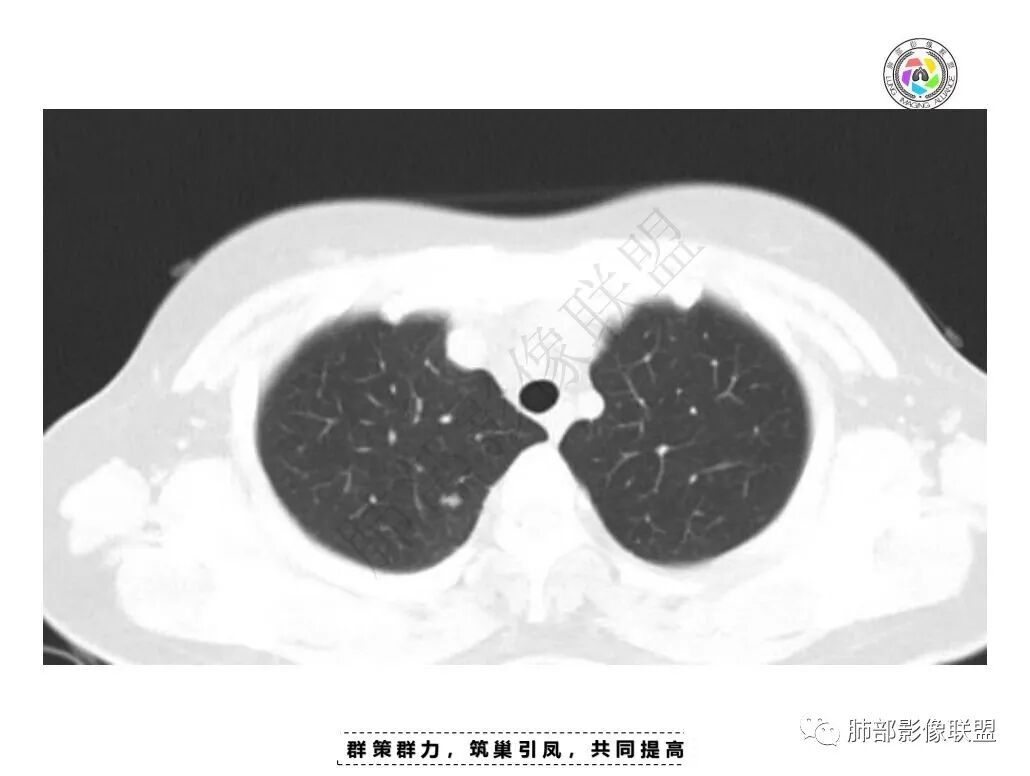

一月后复查,肺内病灶密度增高,边缘收缩,体积缩小,提示渗出朝增生转变;胸膜病灶缩小。

2.肺内多发斑片影,边缘光滑,支持炎性特点,不符合恶性侵犯的特点,一般恶性肿瘤侵犯肺内往往边界不清,复查附近病灶有收缩,更加支持炎性病变;